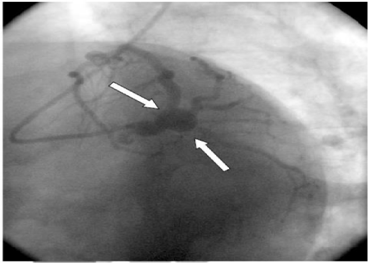

Atherosclerotic Monstrous Double Aneurysm of the Left Main Coronary Artery: A Very Rare Angiographic Finding

Coronary artery aneurysm is a rare disease diagnosed in 0.3 to 4.9% of patients undergoing coronary angiography. The incidence of left main coronary artery aneurysm (LMCAA) is extremely rare: 0.1% [1]. Coronary artery aneurysm involves the right coronary artery, the left anterior descending and circumflex coronary arteries in descending order of frequency [2] and atherosclerosis is the most common cause.